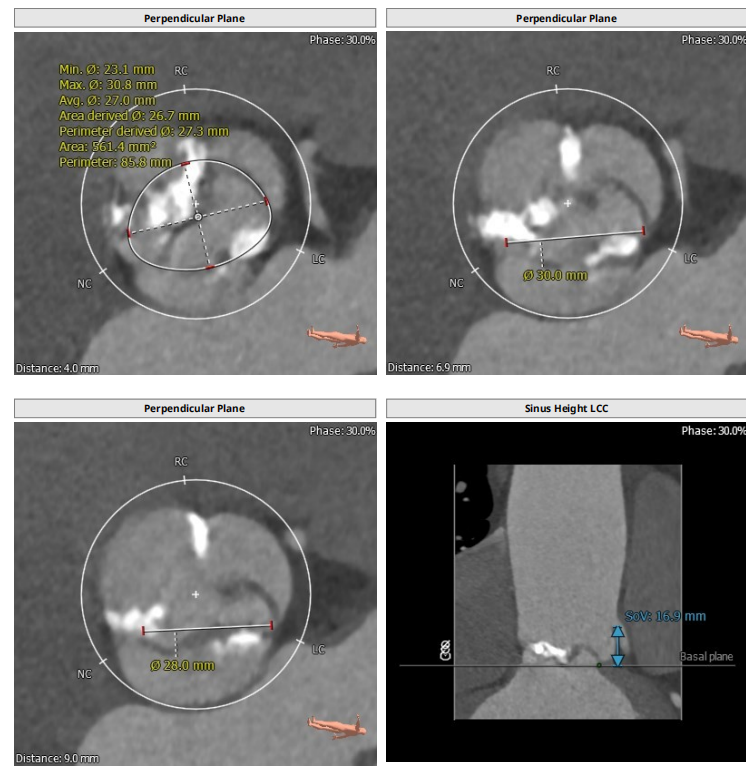

此例病人Type1二叶瓣,左右冠瓣融合,右无疑似融合,重度钙化,瓣环30.5,LVOT33.9,左右冠高度为16.9mm与18.8mm,右无融合离对侧28-30左右,STJ43.7,升主47.9,整体结构极大,心脏角度65度,近乎横位。